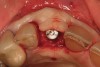

Figure 25  (Case 3) Placement of implants in compromised bone site at removal of No. 10.

Figure 25

Figure 26  (Case 3) Augmentation with demineralized freeze-dried bone allograft.

Figure 26